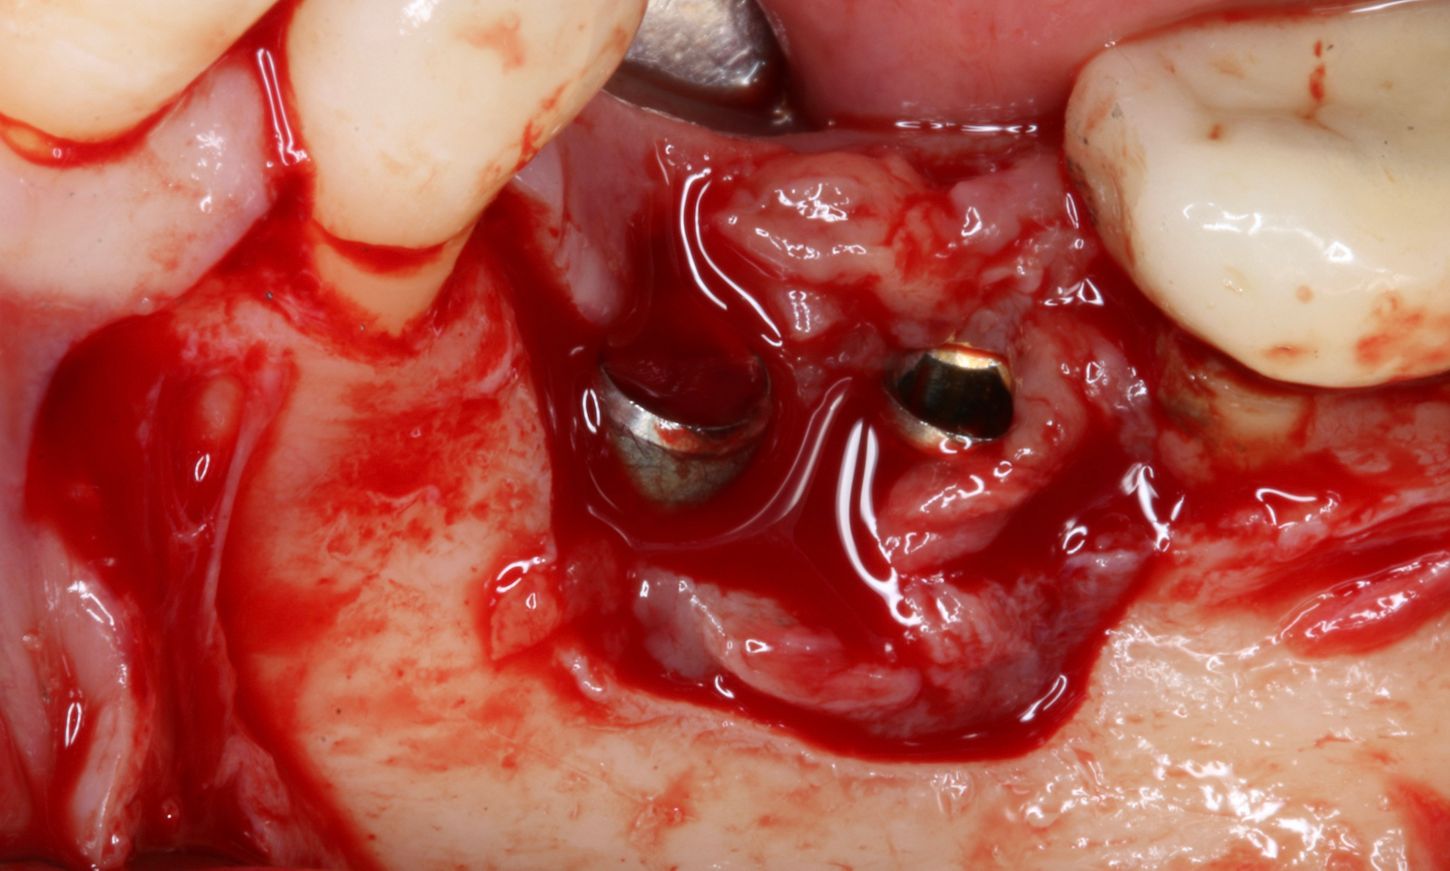

After the non-surgical treatment, clinical examination in 2021 showed a decrease in inflammation, though it was not completely resolved (Fig. 2). Lidocaine 2% with epinephrine 1:100,000 was administered. Upon removal of the prosthesis, the peri-implant mucosa surrounding the implants in positions #36 and #37 exhibited localized inflammation with evident redness, swelling and bleeding (Fig. 3).

Fig. 3

A full-thickness flap was elevated to access the defect and mechanically remove the granulation tissue surrounding the implants (Fig. 4). The bone defect was assessed using the modified criteria established by Monje et al, and was classified as a Class 3b defect, making it suitable for reconstructive therapy. First, implant disinfection was done with ablative mechanical debridement, CHX 0.12 %, metronidazole 5mg/ml, and a solution of local antibiotic and hyaluronic acid (Fig. 5).